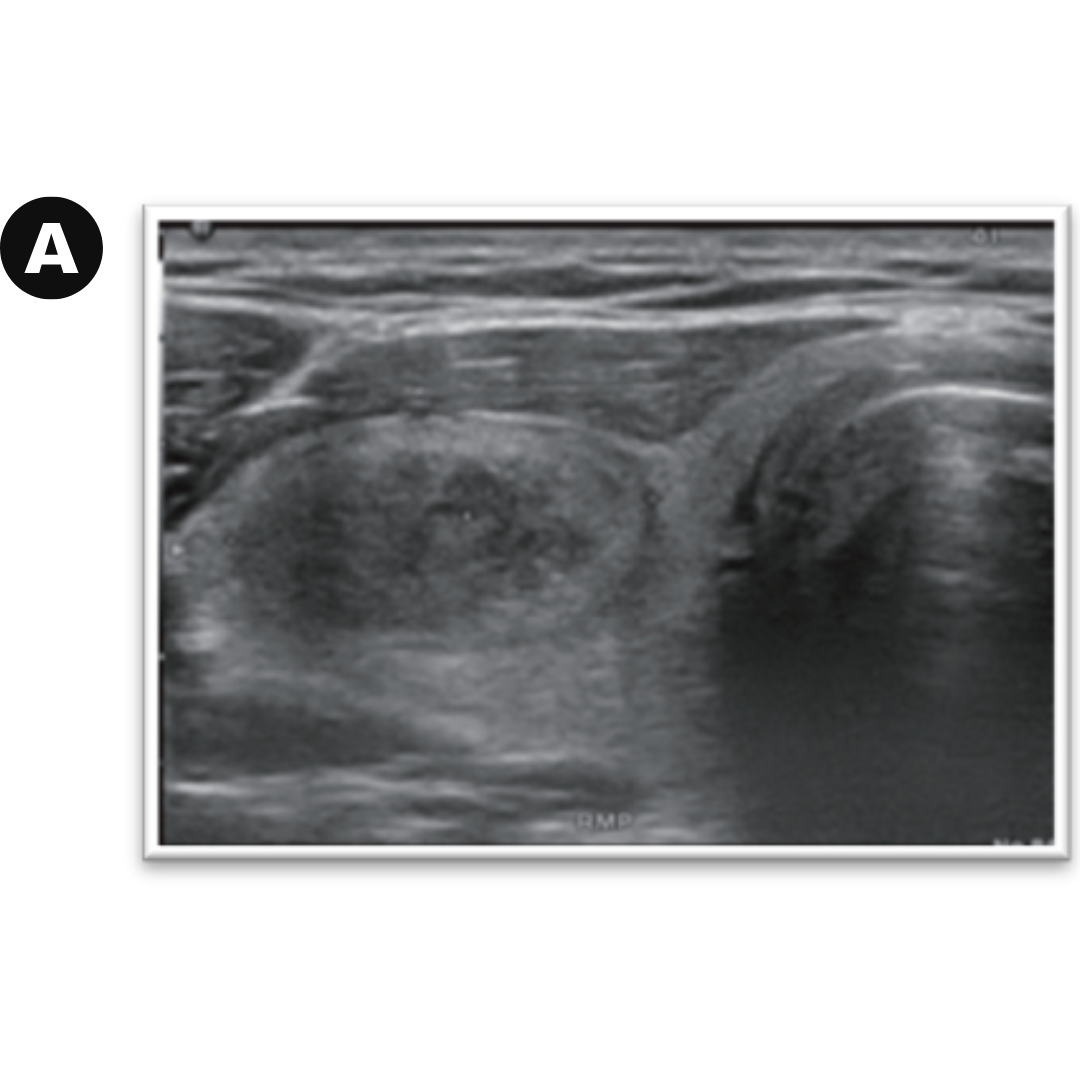

Caso 02: a) Nódulo solido heterogéneo con halo hipoecogénico. b) control a los 3 años siguientes, evidenciando una disminución notoria en su tamaño.